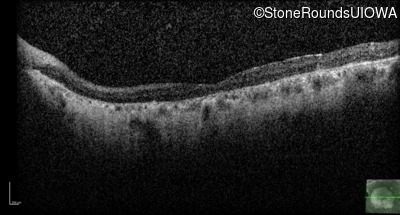

AR Stargardt Disease (IIA)

Age at visit:

70 years

OD

OS

20/32 -1

20/25 -1

AR Stargardt Disease

ABCA4

Gly607Arg GGG>AGG

IVS30+1321 A>G

AR